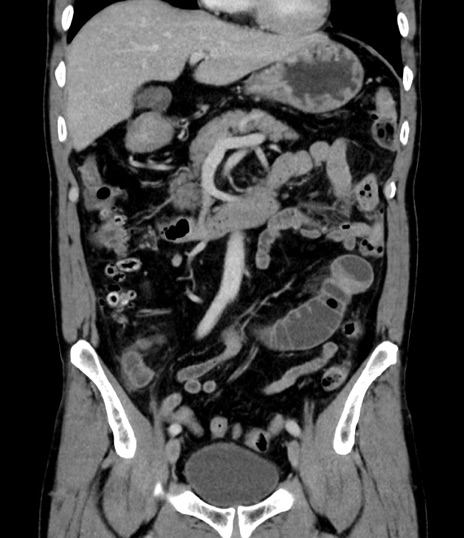

症例8(冠状断像)

【症例】 60歳代男性

【主訴】 黒色吐物

【現病歴】 4日前から嘔気自覚、2日前の朝食後にも嘔気あり、自分で手で嘔吐反射起こし嘔吐したところ血が混ざっていたため受診。

【既往歴】 5年前汎発性腹膜炎を伴う急性虫垂炎で手術、高血圧、前立腺肥大症、高脂血症

【身体所見】 腹部正中に手術癩痕あり 腹部平坦・軟圧痛なし膨満感あり

【データ】WBC 8400、CRP 4.54

横断像